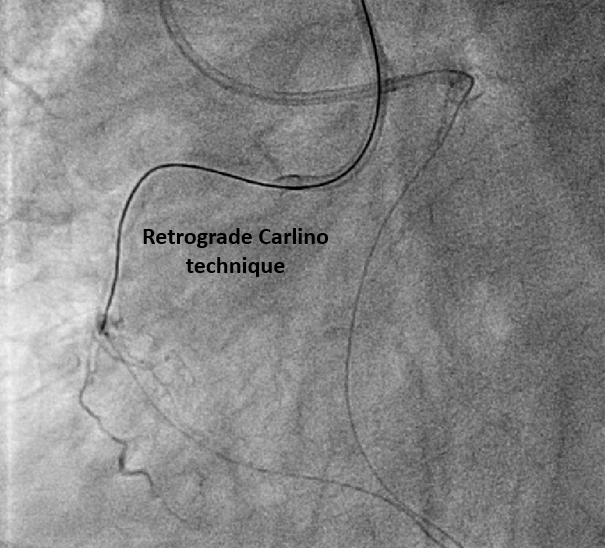

The pLAD ISR was treated first with balloon dilatation followed by DES implantation. An antegrade wire escalation strategy up to Conquest Pro 8-20 for RCA CTO was attempted without success. The wire was left in the subintimal space while a retrograde Sion wire supported by a Finecross microcatheter was advanced through a septal channel to reach the distal CTO cap. The retrograde wire was then exchanged for Gaia 2 and XTA for distal CTO cap penetration. However, a kissing wire technique could not be achieved within the CTO body. Following multiple unsuccessful attempts, the Carlino technique was performed via both the antegrade and retrograde microcatheter. Although a retrograde Fielder FC wire could cross the lesion to the antegrade guiding catheter, this could not be followed by a microcatheter. The retrograde Fielder FC wire was then advanced into the antegrade Tornus microcatheter which also couldn¡¯t cross the lession. Consequently, the retrograde wire was exchanged to RG3. Successful tip-in and externalization with RG3 was achieved afterwards. An antegrade 1.0mm balloon failed to traverse the heavily calcified CTO segment. Therefore, antegrade rotational atherectomy was performed using a 1.25mm burr over the RG3 wire. Following that, the Tornus microcatheter was able to cross the lesion into the distal RCA. A Sion wire was advanced to the distal RCA and the RG3 wire was retrieved. Subsequent balloon dilatation and implantation of two DES were successfully completed

Bi-directional Carlino technique could facilitate intraplaque wire tracking. Usually, after externalisation by RG3 wire, an antegrade microcatheter is advanced distal to the CTO segment for wire exchange, such as a Rotawire in preparation for rotablation. However, in this case, the severe calcification prevented antegrade microcatheter passage. Although the RG3 wire is known to be compatible with rotational atherectomy due to its smaller diameter, its clinical use in this situation is rare. Our case demonstrates the feasibility of performing rotablation over an RG3 wire when neither antegrade nor retroagrde microcatheter passage across the CTO segment is possible.